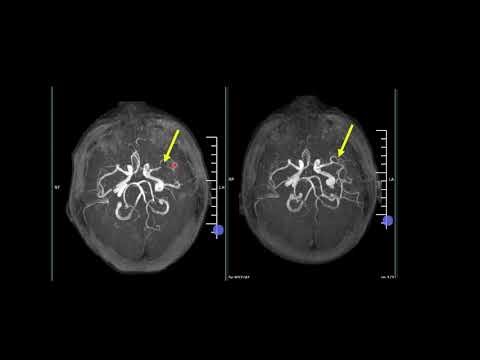

Understanding Arterial Spin labeling MR Perfusion and ADC Reversal

Time-Spatial Labeling Inversion Pulse (Time-SLIP) MRA

ISMRM MR Academy - ASL Advanced Topics (Arterial Spin La

Arterial Spin Labeling (ASL) Basics

ISMRM MR Academy - ASL Basics (Arterial Spin Labeling Basics)

Introducing MRI: Arterial Spin Labeling (54 of 56)